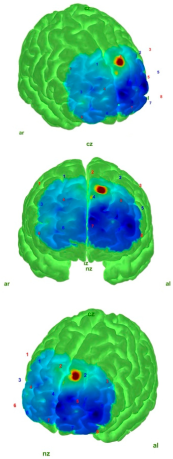

| Control | AIS | |

|---|---|---|

| EO |  |  |

| EC |  |  |